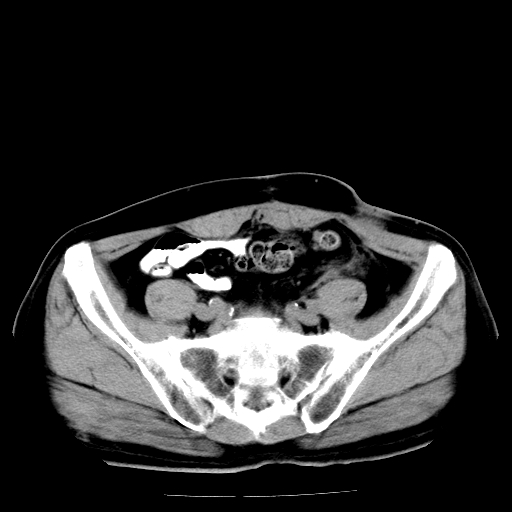

男,66岁,直肠癌术后一个月,化疗前ct检查。

直肠癌造瘘术后改变,周围淋巴结转移

前列腺肥大

直肠癌造瘘术后改变,盆腔多发淋巴结转移

直肠癌造瘘术后改变,直肠周围软组织增厚,盆腔多发淋巴结转移。前列腺肥大。